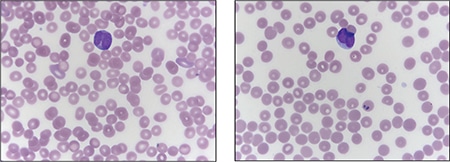

Two morphologic forms of APL are recognized including hypergranular (or typical) and microgranular variants. The blasts of typical APL have irregular large nuclei that can be bilobed and may have a “sliding plate” morphology. The cytoplasm is densely packed with large granules and occasional Auer rods. Microgranular variant blasts mostly have a bilobed morphology, and cytoplasmic granules are not apparent as they are submicroscopic. Cytochemical stains such as myeloperoxidase and Sudan black are strongly positive in both variants, often to the point that the cytoplasmic granules obscure the nucleus.

Case. A 16-year-old male presented with a one-week history of fatigue and easy bruising. Complete blood count revealed a white count of 4.8 × 103/mm3 with left shift of the myeloid lineage with 50 percent blasts, hematocrit of 31 percent, hemoglobin of 10.8 g/dL, and a platelet count of 29 × 103/mm3. Review of the peripheral blood smear showed numerous blasts with increased nuclear-cytoplasmic ratio and bilobed nuclei with sliding plate morphology (Fig. 2). Myeloperoxidase stain performed on the peripheral blood was strongly positive (Fig. 3). The morphologic and clinical findings were concerning for APL and thus the clinical team started ATRA (all-trans-retinoic acid) while awaiting final diagnosis. Flow cytometry revealed the blast population to be dim CD45, bright CD33, subset CD34, dim HLA-DR, dim CD13, CD117, subset CD56, and cytoplasmic MPO positive (Fig. 4). Dual color dual fusion fluorescence in situ hybridization was negative for t(15;17) (Fig. 5).6